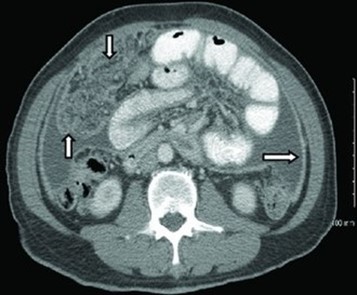

CT scan of peritoneal tuberculosis, with thickened omentum and peritoneal surface

Extrapulmonary tuberculosis (EPTB) is a form of tuberculosis that affects organs or tissues outside of the lungs. It can affect any part of the body, including the skin, lymph nodes, abdomen, bones, joints, genitourinary tract, meninges, and heart. EPTB is less common than pulmonary TB, accounting for approximately 20% of all TB cases.

It is often more challenging to diagnose than pulmonary TB because the symptoms may not be as obvious. Symptoms can vary depending on the location and severity of the infection but may include fever, night sweats, weight loss, and swelling or pain in the affected area.